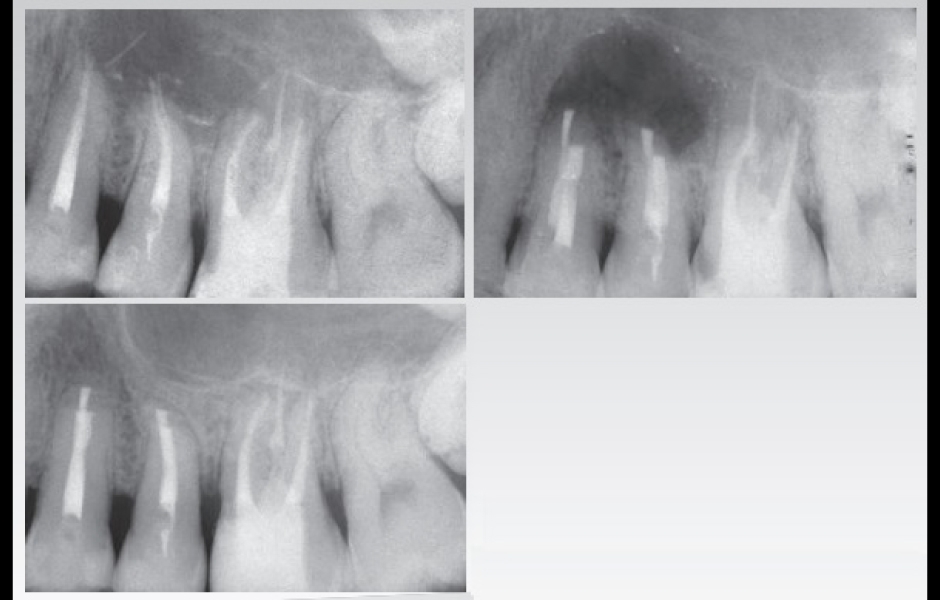

Součástí programu je také výjimečně intenzivní celodenní hands-on kurz endodontické mikrochirurgie. Nejintenzivnější praktický kurz, který byl u nás v tomto oboru organizován, si klade za cíl účastníky doslova vyždímat na retrográdním mikrochirurgickém ošetření až čtyř (!) reálných zubů, od řezáků až po horní i dolní moláry. Cílem organizátora je udělat z hands-on kurzu nezapomenutelný intenzivní zážitek, pro který nemusíte jezdit až do Florencie.

Teoretický koncept prediktabilní mikrochirurgické endodoncie od A do Z, výjimečně intenzivní hands-on kurz s operačním mikroskopem a na skutečných zubech včetně molárů.

Dr. Castellucciho přístup k mikrochirurgické endodoncii je přímočarý a čistý

…a přináší bezpečné a prediktabilní výsledky v podobě úspěšného hojení

Na přihlášené čeká opravdu intenzivní celodenní mikrochirurgický hands-on